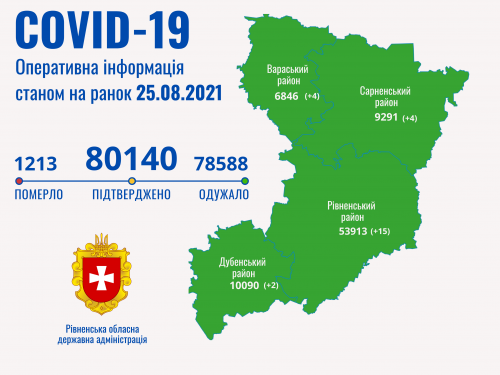

Коронавірус повертається: як стрімко зростає кількість хворих на Рівненщині (ВІДЕО)